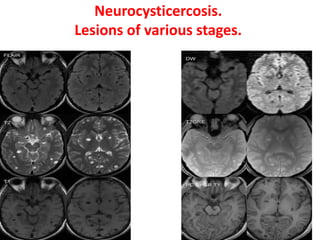

Neurocysticercosis.

Lesions of various stages.